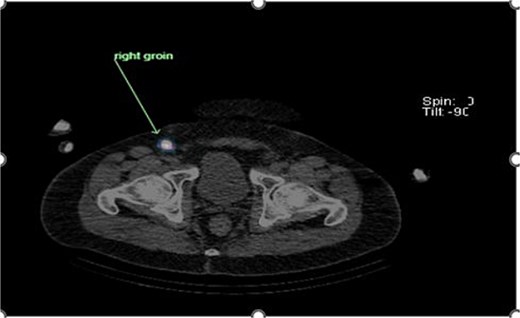

Preoperative lymphoscintigraphy was performed to detect the sentinel lymph node (Fig. 1), expecting it to be in the right inguinal region (Fig. 2). However, drainage to both the right axillary (Fig. 3) and inguinal areas was demonstrated. During surgery, a gamma camera confirmed drainage to both regions (Fig. 4). Blue dye was injected around the previous scar, and sentinel nodes were dissected guided by both blue dye and gamma camera for histopathology.

Unexpected drainage visualized toward the right axillary lymph nodes.